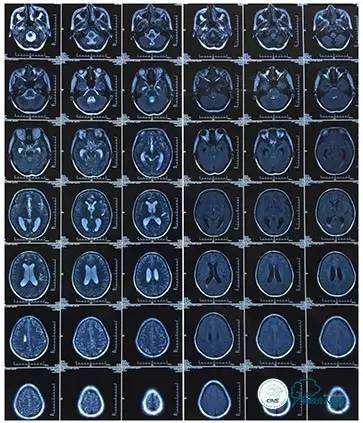

磁共振黑血系列

2016-5-19 MRI

2016-05-20 MRV